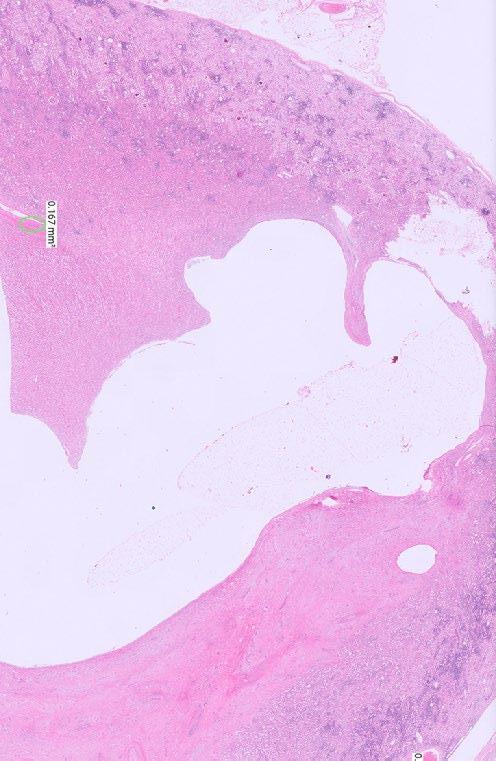

Histopathological Description

The kidney has marked and prominent hydronephrosis alongside a proliferation of dense fibrous tissue (Figure 1) Infiltrating and disrupting the renal cortex, is an invasive mass composed of neoplastic large and polygonal epithelial cells arranged in anastomosing trabeculae and cords associated with a scirrhous response (Figures 2-3). Neoplastic epithelial cells have infrequent to rare foci of individual keratinisation (Figure 2) and prominent intercellular spinous processes (Figure 3), typical of cells of squamous origin.

Figure 1. Low power photomicrograph of the kidney showing marked hydronephrosis and effacement of the medulla towards the right of the dilated renal pelvis by abundant amounts of dense fibrous tissue

Figure 2. Anastomosing trabeculae and cords of invasive neoplastic epithelial cells are present within the cortex associated with a dense and scirrhous fibrous reaction towards the left of the photomicrograph. Black arrows show infrequent to rare foci of individual cell keratinisation.